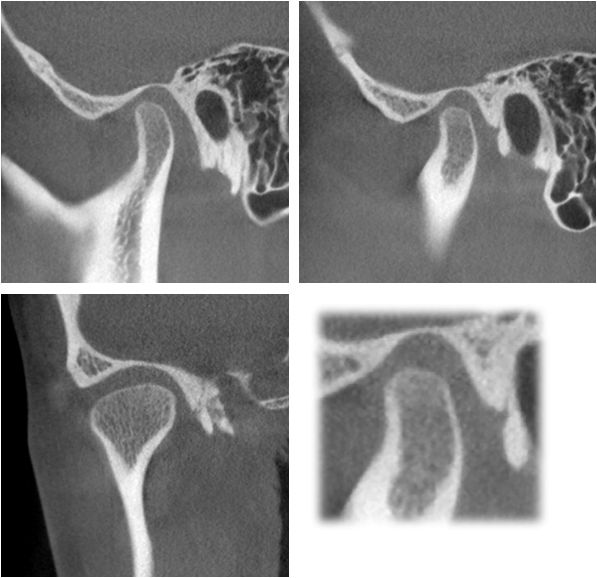

CBCT检查:

从患者双侧颞下颌关节的ct断层影像上看,右侧关节前间隙明显偏小,髁突表面骨皮质较连续但厚度较薄,右侧关节间隙较均匀,个别断面上,髁突表面的骨皮质较粗糙,不明显。左侧颞下颌关节髁突表面骨皮质模糊粗糙,厚度较薄,关节间隙较均匀。临床功能检查上,患者开口度开口型正常,双侧关节张口中期有弹响。

右侧颞下颌关节髁突表面骨皮质连续均匀,关节间隙均匀。左侧颞下颌关节髁突表面骨皮质增厚,个别吸收点消失,关节间隙较均匀。